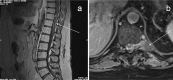

Case report: A 33-year-old man with a history of infracentimetric carcinoma of the lip developed back pain associated with progressive neurological disorders leading to paraplegia. This atypical presentation led to initial misdiagnosis, but radiological and cytological explorations finally confirmed the diagnosis of leptomeningeal and intramedullar secondary spinal cord lesions from his previously treated head and neck SCC. Systemic targeted therapy with epidermal growth factor receptor inhibitor and intrathecal chemotherapy led to prolonged disease stabilization.